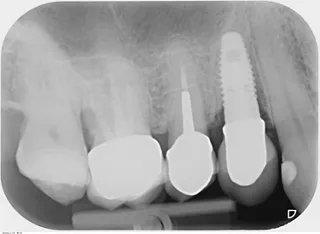

Die Röntgenaufnahme zeigte distal und mesial des Implantats einen mittelschweren vertikalen und horizontalen Knochenverlust (Abb. 1).

Abb. 01